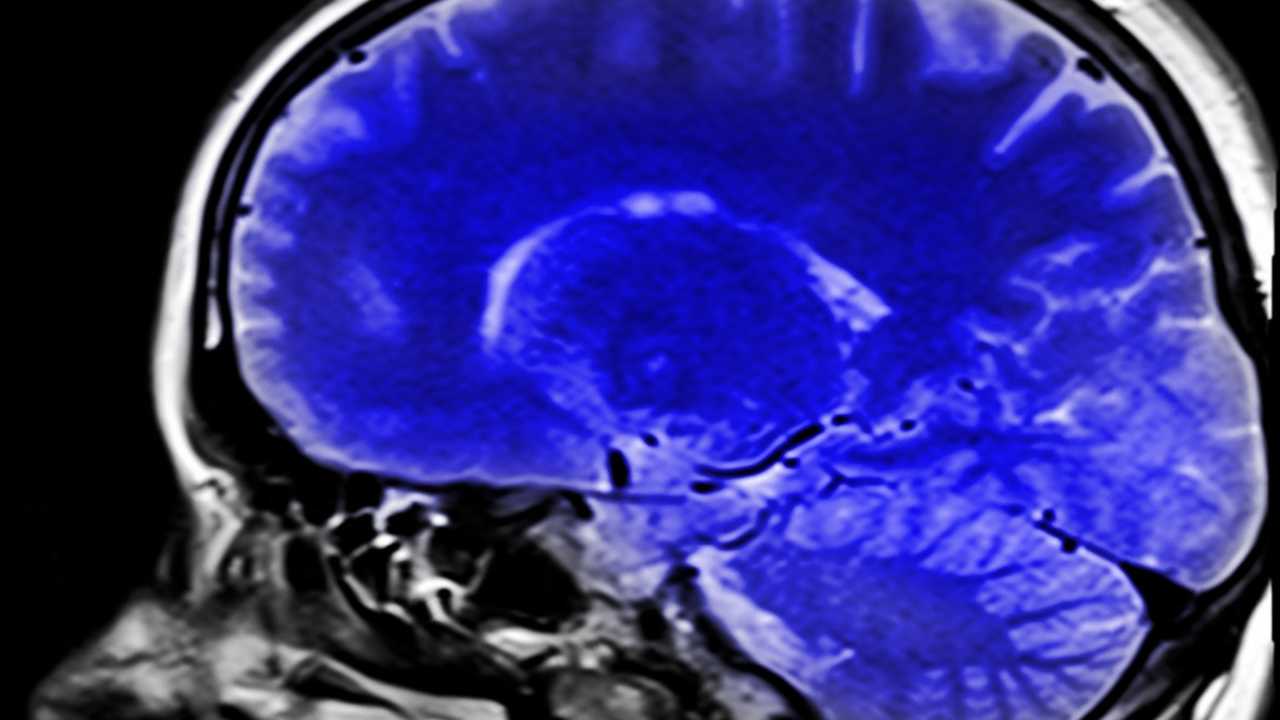

Исследование стало одним из первых, где с помощью МРТ, ПЭТ и поведенческих тестов комплексно оценили влияние аспартама при долгосрочном употреблении в дозах, сопоставимых с обычным рационом человека. Эти данные ставят под сомнение безусловную безопасность подсластителя и указывают на необходимость более глубокого изучения его воздействия на сердце и мозг.